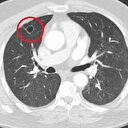

İstanbul’un en büyük Kovid merkezlerinden biri olan Göztepe Süleyman Yalçın Şehir Hastanesi’nde acile başvuran, serviste takip edilen ya da yoğun bakıma kaldırılmış hastalar üzerinde yapılan bir çalışma, virüsün kısa bir süre içinde vücudu kanser ve kalp hastalıklarından koruyan protein düzeylerini çok düşürdüğünü ortaya koydu. Üstelik Kovid’i ağır geçiren hastalarda bu protein düzeylerinin eski haline dönemediği de gösterildi. Kovid-19’un yarattığı bu etkiyi dünyada ilk kez ortaya koyan araştırma, dünyanın en büyük kalp kongresi olan Amerikan Kalp Derneği’nin kongresinde de ödül aldı.

Çalışmayı yürüten ekipten Prof. Dr. Mehmet Ağırbaşlı, “Hastanemize başvuran 180 hastanın metabolik verilerini izledik. Kovid-19’a yakalanan kişilerde savunma proteini düzeyi çok kısa bir süre içinde ‘şalterler kapanırcasına’ çok düşük düzeylere iniyor. Koruyucu protein disfonksiyonu, kalp hastalıkları ve kanserde hastalık oluşumunda etkisi büyük. Kovid’e yakalanan kişilerin ileride kanser ve kalp hastalıklarına yatkınlığı artacak mı, bu çok önemli bir soru” dedi. Prof. Dr. Ağırbaşlı, “Vücudun metabolik stres anlarında kullandığı belli savunma mekanizmaları var. Bunlar da belli koruyucu proteinler içeriyor. Bu koruyucu proteinleri hastanemizde acile başvuran, servislerde veya yoğun bakımda yatan hastalarda araştırdık. Gördüğümüz şey çok şaşırtıcıydı çünkü Kovid-19, hastalığa yakalanan kişilerde çok kısa bir zaman içinde koruyucu protein düzeylerini düşürerek vücudu savunmasız bırakıyor. Hastalık ilerledikçe vücut, savunma mekanizmalarını yeniden oluşturmaya çalışıyor fakat normale dönmüyor” şeklinde konuştu.

Ağırbaşlı şöyle devam etti: “Vücudun kendisinin ürettiği, pıhtılaşmaya karşı koruyucu olan proteinler var yine. Bunların da Kovid-19’da aşağı gittiğini görüyoruz diğer çalışmalardan. Biz, kendi çalışmamızda ise LRP1 diye bir moleküle baktık. Bunun ateroskleroz (damar sertliği), inflamasyon ve pek çok hastalıkta koruyucu olduğunu biliyoruz. Kovid geçiren hastalarda bu molekülün hemen hemen yok denecek kadar azaldığını gördük. Dünyada baktığınızda, neredeyse yarım milyar insan bu hastalığa yakalandı ve iyileşti. Bu kadar çok insanı etkileyen bir hastalık eğer (kalp, kanser gibi) kronik hastalık risklerini artırırsa bu ileride, sağlık sistemlerinin de baş edemeyeceği düzeyde bir yük getirecektir.”